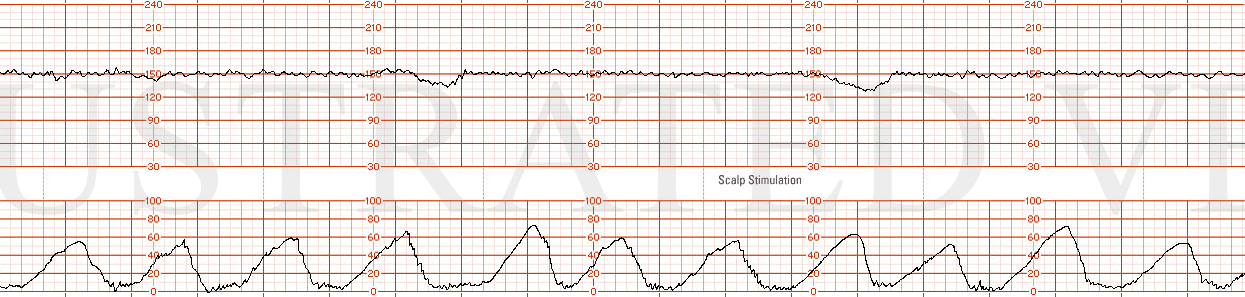

Excessive Uterine Activity

Unfortunately, the influence of uterine activity has not been sufficiently addressed in the literature. Excessive uterine activity may adversely affect a fetus, demonstrated by decreased variability, late decelerations, and prolonged decelerations. Additional authors consider excessive uterine activity as the most frequent cause of late decelerations (Freeman and Sheaker). Fetal outcomes were examined, and increased uterine activity during the first and second stages of labor was associated with a higher incidence of lower umbilical artery pH. Increased uterine activity was significantly associated with a higher incidence of umbilical artery pH of 7.11 or less.

Illustrated Verdict, Inc. 04-Case35N

Physical evidence for uterine activity-induced fetal acidosis at birth included the following observations: when uterine contractions were >30mmHg. The maternal uterine spiral arteries were compressed, and "placental perfusion was strangulated. ".6 Maternal pushing efforts increased intrauterine pressure, which resulted in further compression of the spiral arteries. Excessive uterine activity also led to hyperstimulation and tachysystole by shortening the relaxation time between contractions. These negative effects were noted during the last hour of the first stage of labor and the entire second stage.7

Uterine contraction monitoring is rarely mentioned, but studies have shown that it may deserve full attention as it pertains to adverse fetal outcomes. Uterine activity monitoring deserves a more prominent role in day-to-day obstetrical practice.8